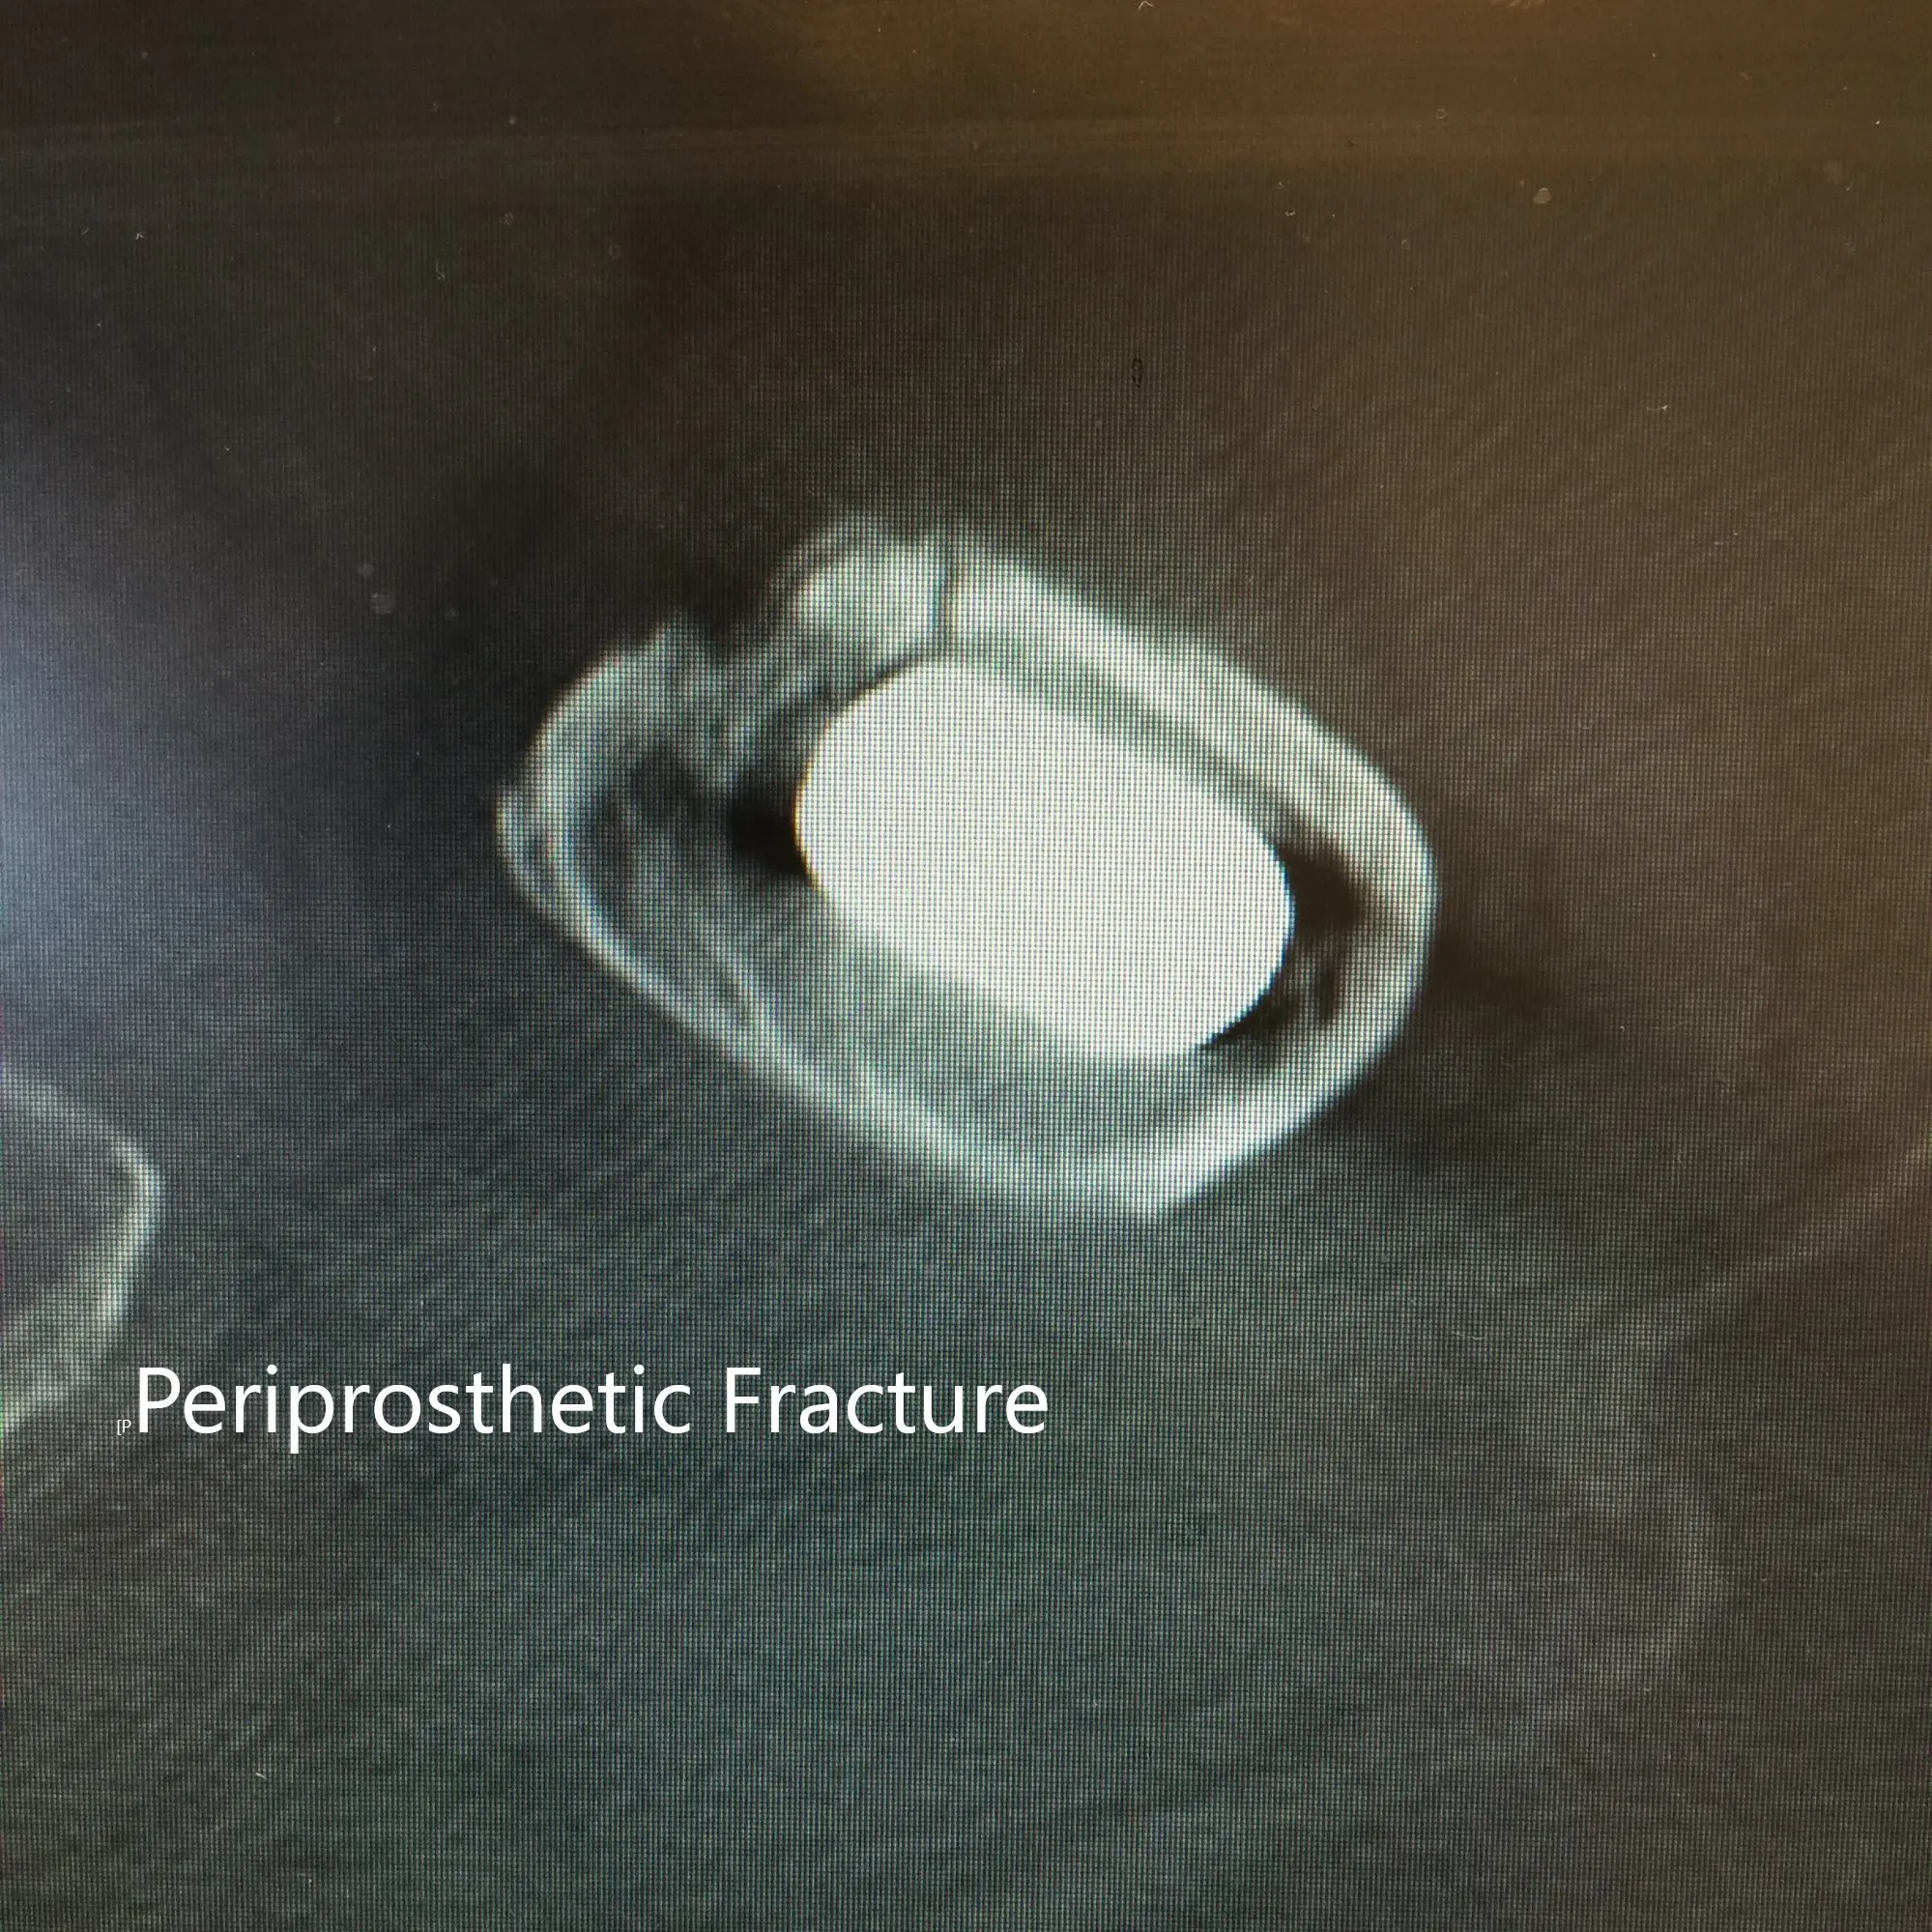

CT scan and X-ray of the left hip revealed a nondisplaced periprosthetic fracture of the proximal femur anteromedially with subsidence of the stem.